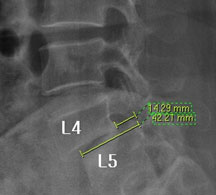

모커리한방병원 조○○ (79, 여) 척추전방전위증 2단계 실제치료사례 이미지

조○○ (79, 여) 척추전방전위증 2단계 입원치료기간 : 28일

입원시 퇴원시

허리 통증지수(NRS) 8 0

엉덩이 통증지수(NRS) 7 0

통증없이 걷는거리(m) 20m(보조기 착용) 150m(보행기 없이)